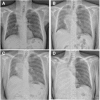

Background: Tracheobronchial malignant stenosis is a life-threatening condition which may cause recurrent infections due to lung atelectasis. Despite immunotherapy is less toxic than standard chemotherapy, recurrent lung infections may represent a challenge for this treatment. We report a clinical case of a patient with metastatic squamous cell carcinoma suffering from pulmonary infections due to central airway obstruction who underwent endoscopic recanalization followed by immunotherapy. VSports手机版.

Case presentation: A 64 year-old man was referred to our attention for the management of metastatic squamous cell carcinoma obstructing the right main bronchus with recurrent pulmonary infections. Patient exhibited strong positive PD-L1 expression (> 50%) V体育安卓版. Advanced disease stage contraindicated surgical treatment. Although therapy with immune check point inhibitors was indicated as first-line treatment, recurrent pulmonary infections made it unfeasible. Therefore, we planned a combined approach including endoscopic recanalization of central airway in order to resolve lung atelectasis, and lung infection followed by immunotherapy treatment with pembrolizumab in order to avoid local and systemic disease progression. .

Conclusions: At 16-week follow-up, the patient was alive in stable disease with improvement of clinical condition and no signs of lung infection. V体育ios版.